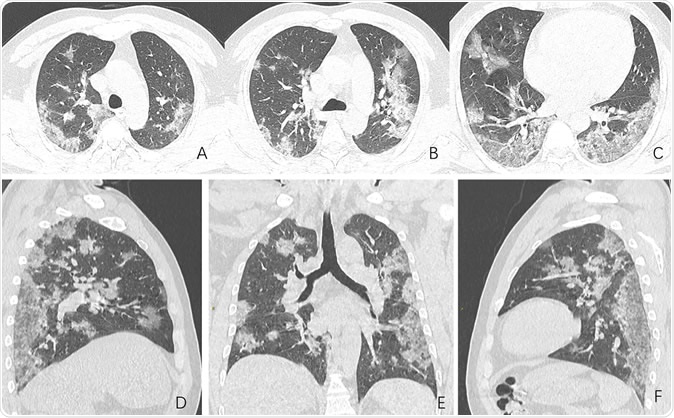

Images in a 44-year-old man who presented with fever and suspected COVID-19 pneumonia. A-C, Thin-slice (1-mm) axial CT images showed multiple patchy ground-glass opacity along the peribronchial and subpleural lungs. Some reticular opacities were also found within areas of ground glass (crazy-paving pattern). Lymphadenopathy was absent. D-F, Multiplanar reconstruction showed diffuse distribution of lesions.

The study examines the chest X-rays, and CT scans from over 20 patients aged 10-74 years, with symptoms of COVID-19. The scans showed inflamed lungs with ground-glass opacities, which look like white lung patches. These opacities are due to the partial clogging of the lung alveoli with tenacious mucus. Autopsies of Chinese patients who died of the illness because of breathing difficulties show lungs with minimal capacity for air inhalation due to the mucus accumulation.